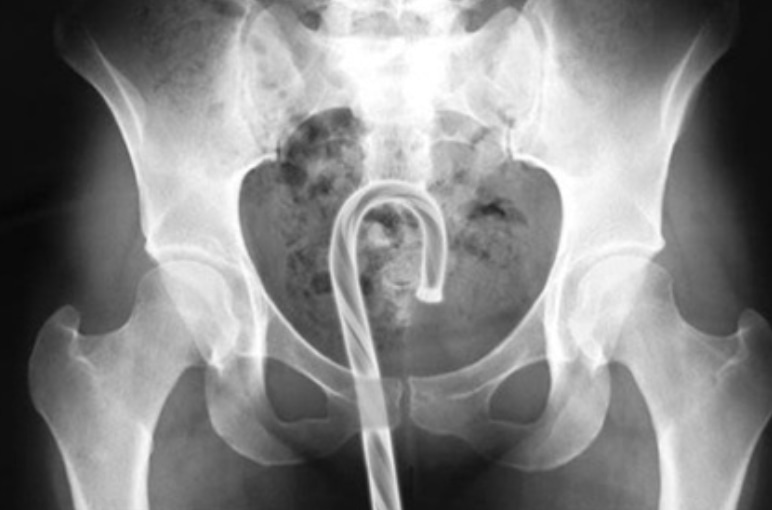

Вытаскивали нетипичные предметы и из более деликатных мест. За 2017 год медики извлекли из пациентов пластиковую ложку, коаксиальный кабель, кость домино и десятисантиметровую секс-игрушку.